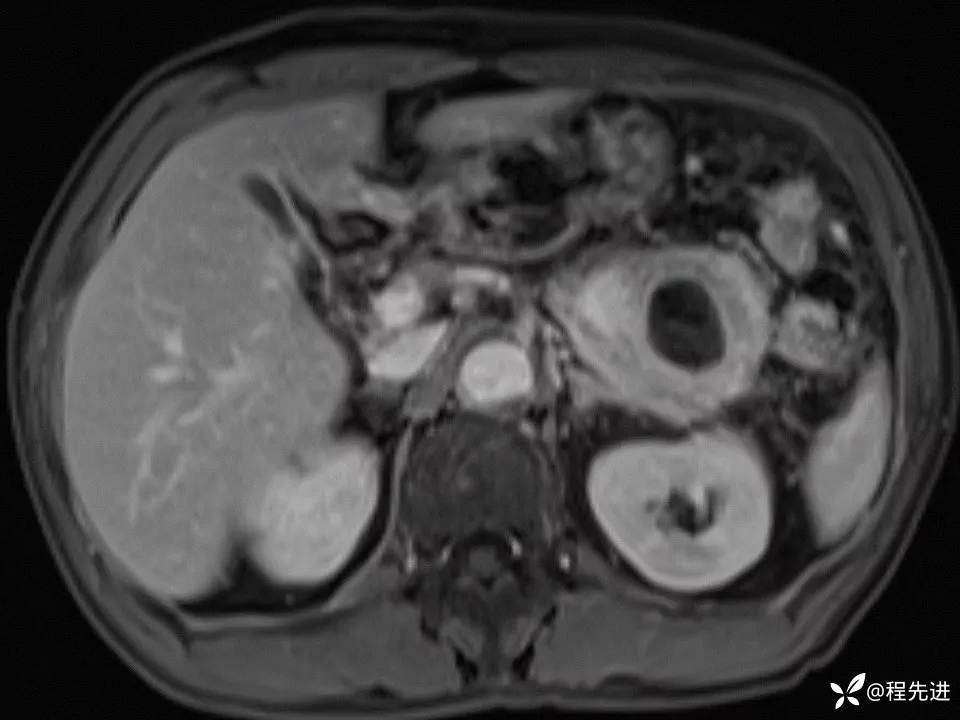

患者性别:男

患者年龄:61岁

简要病史:体检发现胰腺占位

MRI平扫+增强: